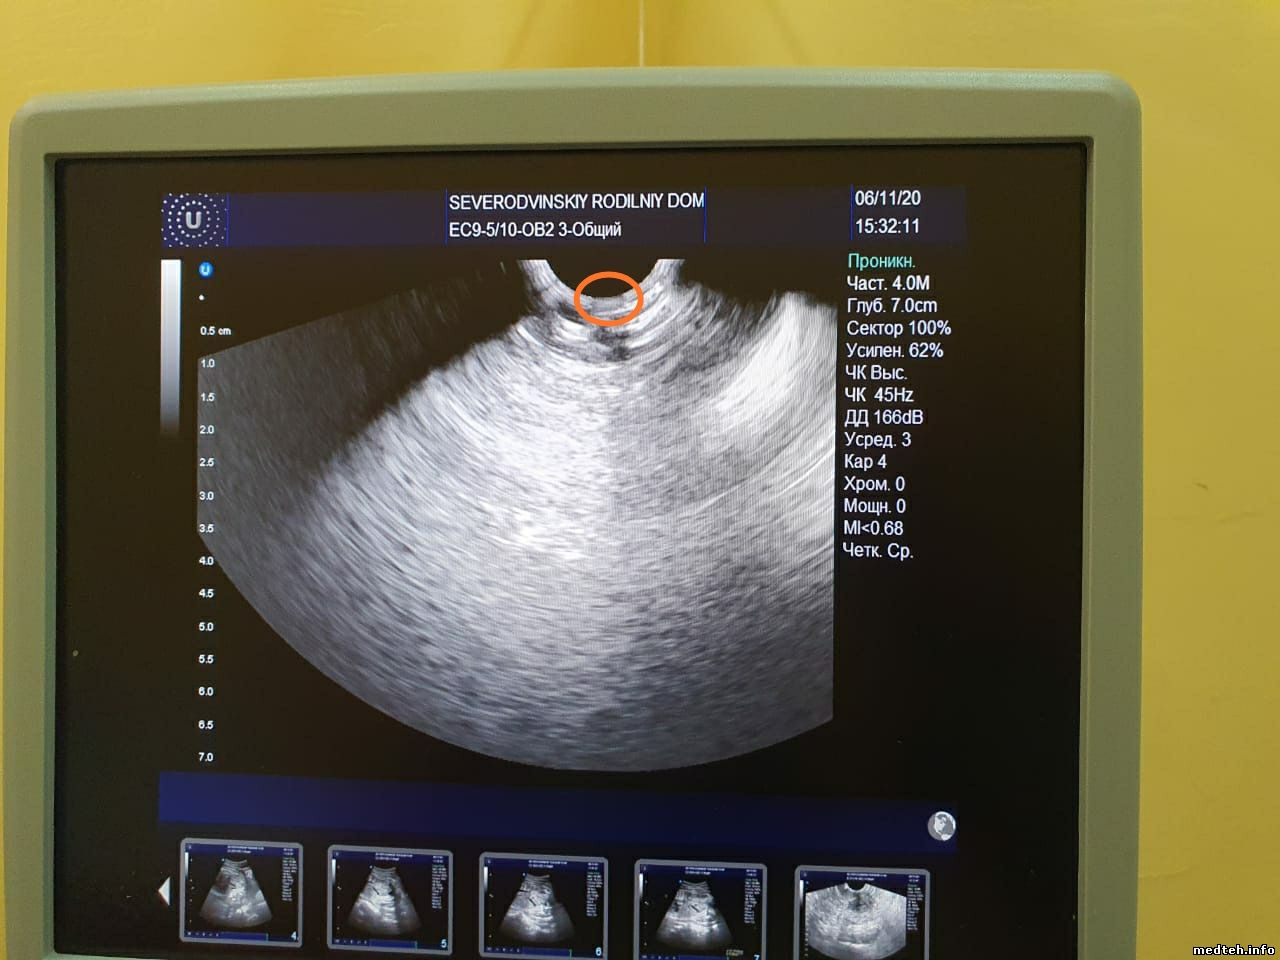

Добрый день!

Подскажите, пожалуйста, в чем может быть проблема с датчиком?

На изображении сверху заметен сектор темнее остальных, создающий своего рода "тень", врачам мешает. При движении металлического предмета по поверхности линзы сектор в этом месте не исчезает, но тускнеет(менее яркий,чем в других частях сектора). Датчик вагинальный. С краю имеется небольшое повреждение линзы. В этом месте дефекта на изображении нет.

5377470.jpg (120.8 Kb) · 4425392.jpg (114.1 Kb) · 4316324.jpg (72.2 Kb) · 5838587.jpg (119.7 Kb)